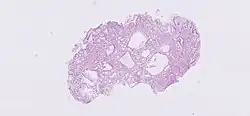

Glândula gástrica

As glândulas gástricas estão localizadas em diferentes regiões do estômago. Estas são as 'glândulas fundicas' ', as' glândulas cardíacas 'e as' 'glândulas pilóricas' . As glândulas e as fossas gástricas estão localizadas na mucosa gástrica. As próprias glândulas estão na lâmina própria da membrana mucosa e se abrem para as bases das fossas gástricas formadas pelo epitélio.[1] As várias células das glândulas secretam muco, pepsinogênio, ácido clorídrico, fator intrínseco, gastrina e bicarbonato.

Os três tipos de glândula estão todos localizados abaixo das fossas gástricas dentro da mucosa gástrica - a membrana mucosa do estômago. A mucosa gástrica está repleta de inúmeras fossas gástricas que abrigam 3-5 glândulas gástricas.[2][3]